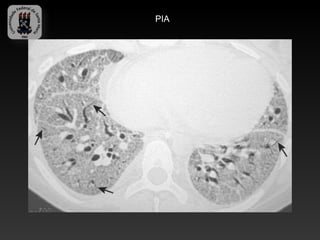

-PNEUMONIA INTERSTICIAL AGUDA

-Dispnéia e hipoxemia, associado dano alveolar difuso.

-Achados TC:

-   Densidades esparças bilaterais

-   Progressão para padrão alveolar difuso.

PIA